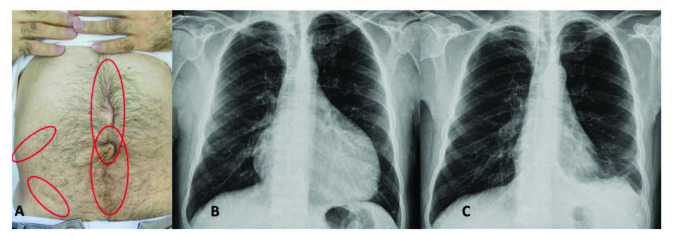

腹膜發(fā)作開始局限并迅速蔓延至整個腹部。腹膜炎癥會導(dǎo)致典型的腸梗阻癥狀,患者會遭受嚴(yán)重的胃痛。體格檢查顯示腹部肌肉僵硬、反跳痛和腸鳴音消失——臨床上這種緊急情況與急腹癥的手術(shù)原因無法區(qū)分。因此,隱匿性腹部手術(shù)史在良性陣發(fā)性腹膜炎患者中很常見(圖 1A)。在疑似病例中,影像學(xué)檢查可能有助于排除手術(shù)病理。腹部發(fā)作后可能會出現(xiàn)輕度反彈性腹瀉。盡管有戲劇性的表現(xiàn),但腹膜炎的所有體征和癥狀在 24-72 小時(shí)內(nèi)有效消退,沒有后遺癥,盡管慢性腹水和腹膜粘連的報(bào)道很少。

包含圖片、插圖等的外部文件。對象名稱為 turkjmedsci-50-1591-fig001.jpg

圖1:(A) 一位因多次腹部手術(shù)而留下疤痕的患者,(B) 胸部 X 光片顯示大量心包積液,(C) 同一患者用阿那白滯素治療后的胸部 X 光片。

心包炎是一種罕見病癥,見于 1%–2% 的患者。心包炎會出現(xiàn)胸骨后胸痛和呼吸困難等癥狀。心包填塞可能很少發(fā)生。心電圖顯示 ST 段抬高,胸部 X 光片可能顯示心臟輪廓的短暫擴(kuò)大(圖 1B 和 1C),超聲心動圖顯示心包積液。在極少數(shù)情況下,反復(fù)性心包炎可能是良性陣發(fā)性腹膜炎的少有表現(xiàn),這可能與特發(fā)性心包炎相混淆 。